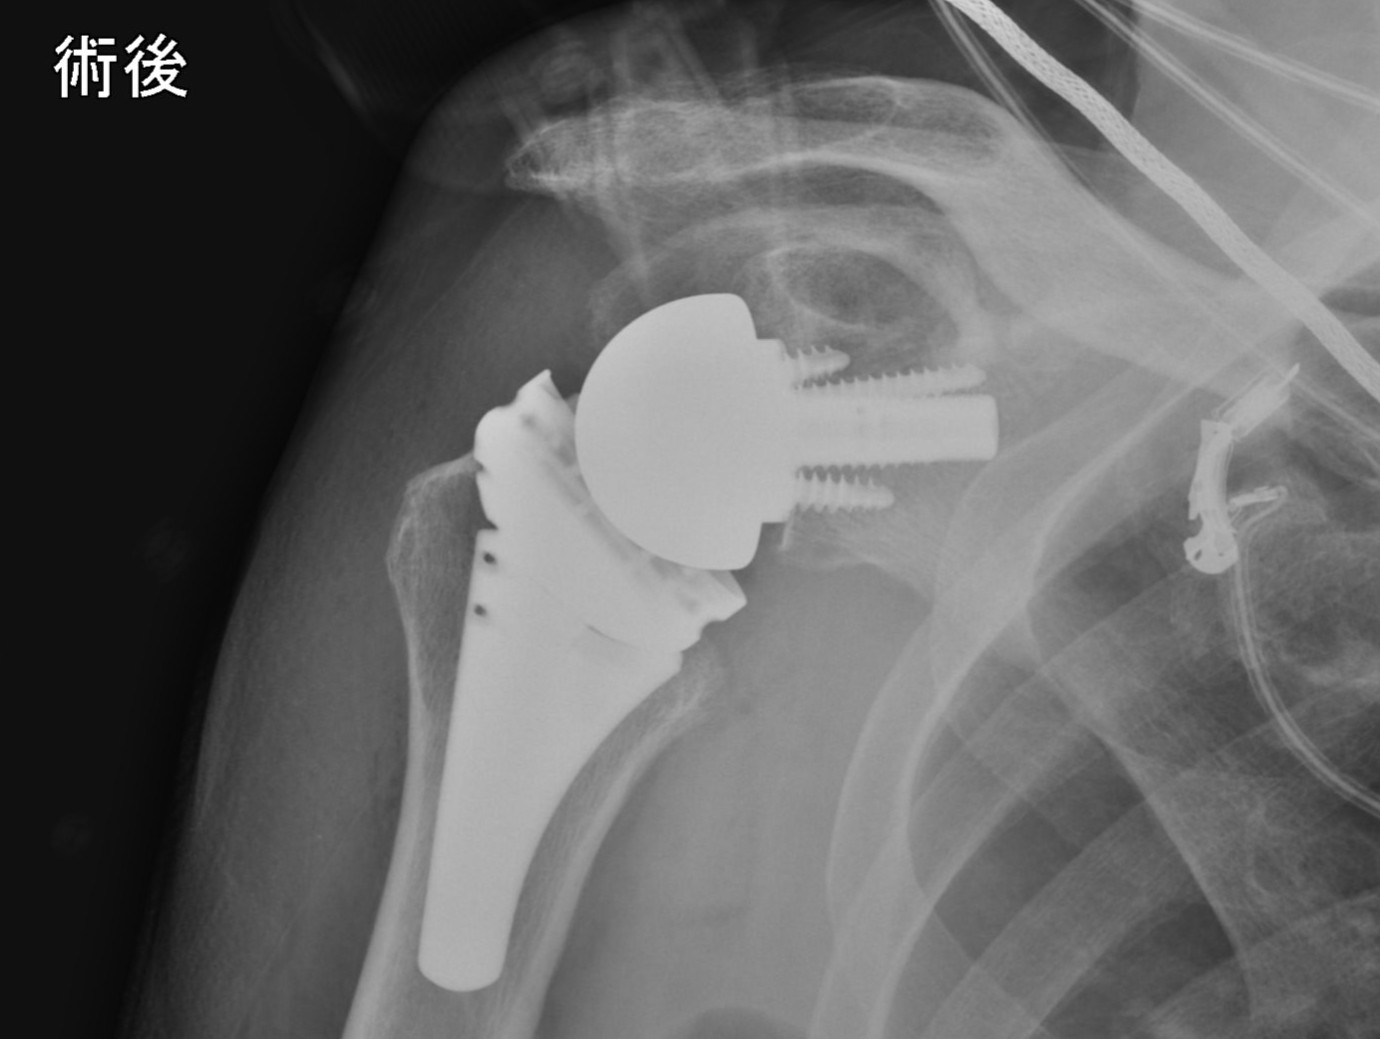

腱板断裂は70歳前後で肩関節痛をきたす疾患の代表であり、注射やリハビリなどの保存加療に抵抗する場合に手術が適応されます。修復可能な場合や65歳未満の若年者では鏡視下修復術が行っておりますが、当院では基礎的データから裏打ちされた最新の治療として、生体材料や自家腱に滑膜由来細胞を導入して補強する独自の手術を行っており、良好な手術成績を国内だけでなく海外にも報告しております。一方、65歳以上で広範囲に断裂しているため一次修復が困難なケースにはリバース型人工肩関節置換術の適応があります。

高齢者の広範囲腱板断裂に対するリバース人工肩関節

術後レントゲン写真